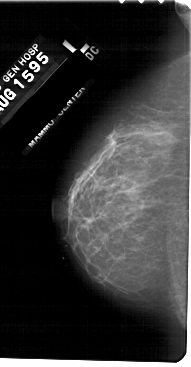

A_1310_1.LEFT_CC

LEFT_CC LINES 5491 PIXELS_PER_LINE 2851 BITS_PER_PIXEL 12 RESOLUTION 43.5 NON_OVERLAY